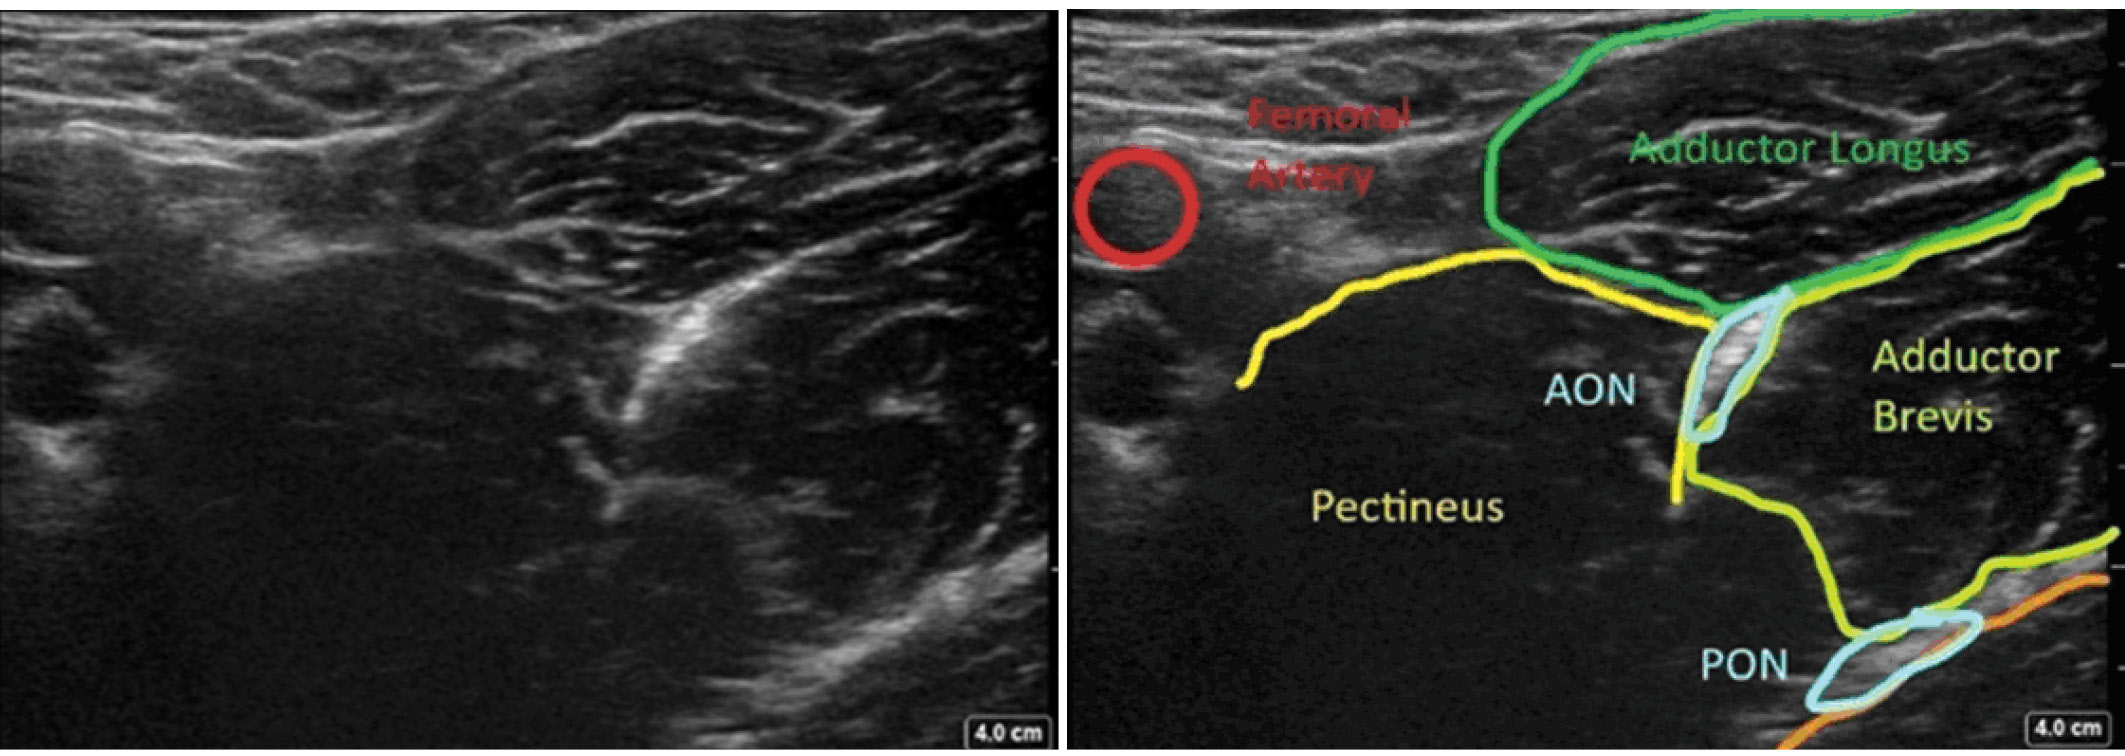

Блокада передней и задней ветвей запирательного нерва (дистальный доступ)

Пациент находится в положении лежа на спине, бедро несколько отведено и ротировано кнаружи. Ультразвуковой датчик помещают в паховую складку и смещают в медиальном направлении (рис. 3) от проекции крупных сосудов бедра до тех пор, пока не будут видны гребенчатая, длинная приводящая и короткая приводящая мышцы. Передняя ветвь запирательного нерва расположена внутри этого типичного «мышечного треугольника». Задняя ветвь расположена между короткой и большой приводящими мышцами (рис. 4). Как правило, и передняя, и задняя ветви запирательного нерва выглядят как гипер-эхогенные структуры.

Рис. 4. Дистальный доступ к блокаде запирательного нерва с визуализацией переднего и заднего отделов запирательного нерва [18]. АОN – передняя ветвь запирательного нерва; PON – задняя ветвь запирательного нерва

Fig. 4. Distal approach the obturator nerve block with visualization of anterior and posterior divisions of the obturator nerve [18]. AON – anterior division of obturator nerve. PON – posterior division of obturator nerve

Раствор местного анестетика вводят между гребенчатой и короткой приводящей мышцами или между длинной и короткой приводящими мышцами [28, 29]. Важно, чтобы раствор местного анестетика распространялся в межфасциальном пространстве, а не в самих мышцах.